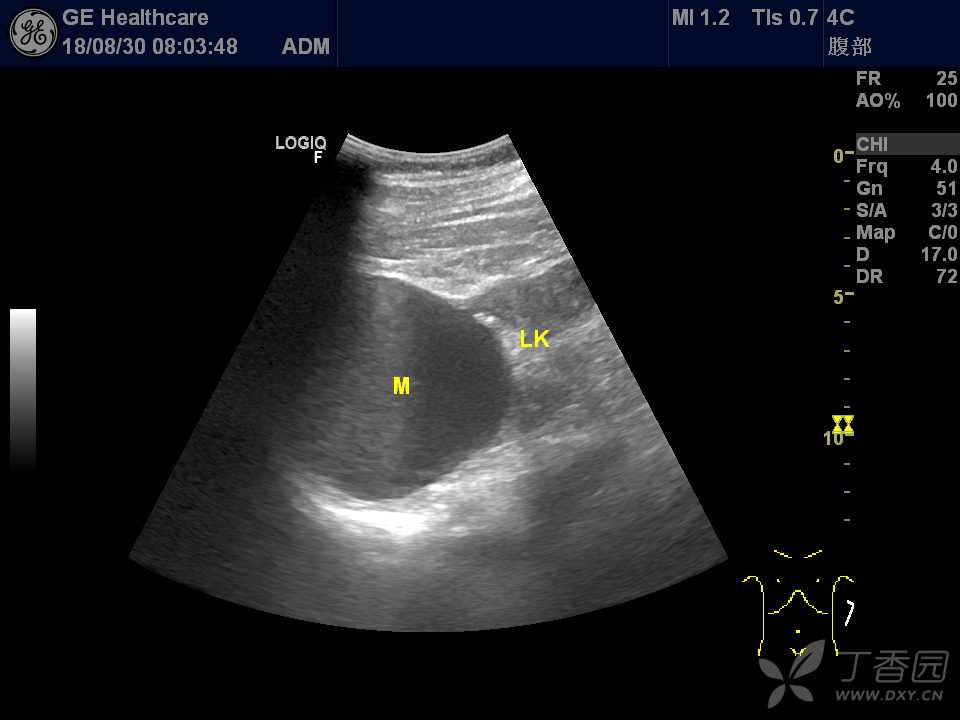

肾囊肿

孤立性肾囊肿